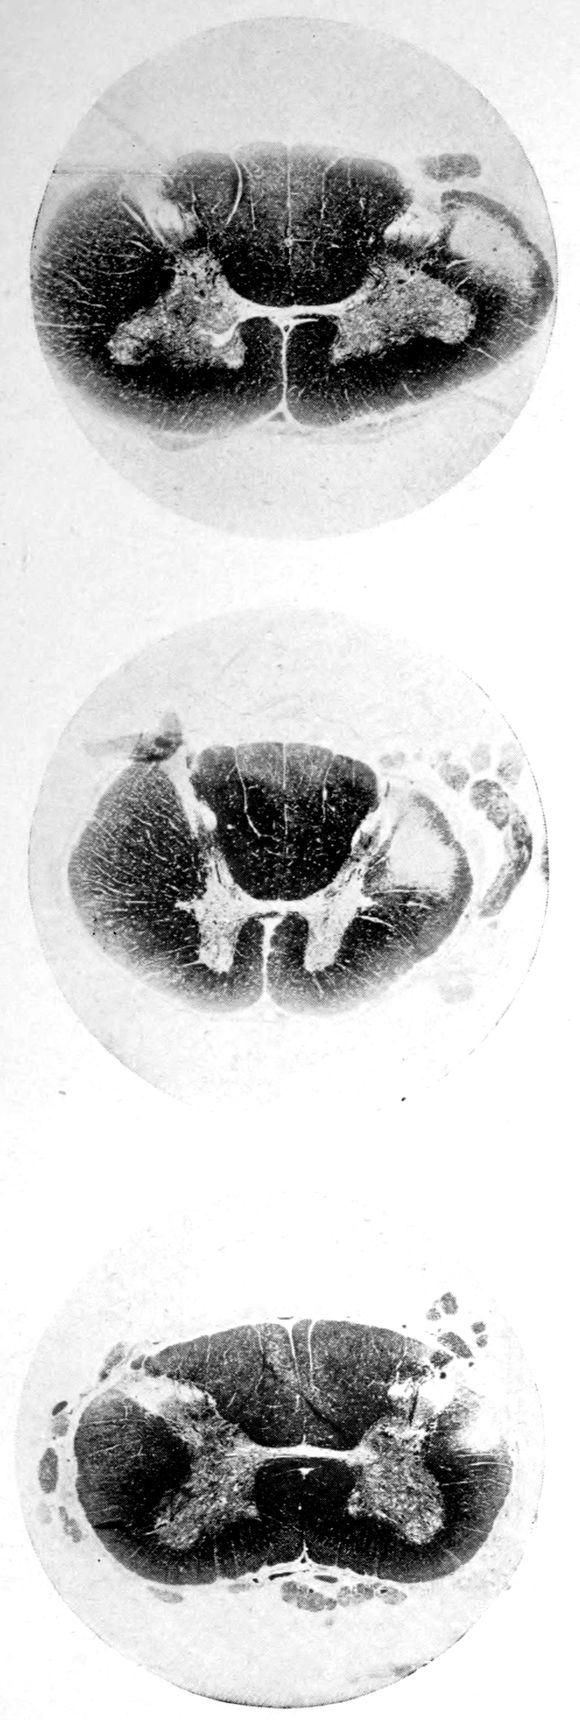

Case I. Spinal Cord (Three Levels) Showing:

A. Marginal sclerosis—effect of old meningitis now extinct.

B. Posterior column sclerosis—effect of meningitis about posterior roots also now extinct.

C. Bilateral pyramidal tract sclerosis—effect of cerebral thrombotic lesions.

Note distortion of tissues in B and C, partly artificial (tissues in places diffluent).

Vascular neurosyphilis—effects of syphilitic thrombosis of Sylvian artery 10 years before death. (Case 4.)

Case 4. (See previous figure for brain lesion.) Three levels of the spinal cord showing unilateral pyramidal tract sclerosis, 10 years after cerebral thrombosis.